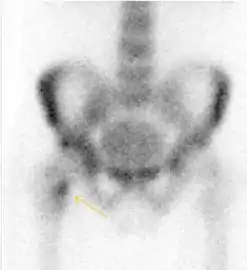

Radiological signs of transient osteoporosis of the hip include localized osteoporosis of the femoral head and neck (Figure 8). Nevertheless, final diagnosis has to be made with MRI to differentiate it from avascular necrosis and from insufficiency or stress fractures of the femoral head or neck. In case of AVN, radiographs can only demonstrate delayed or advanced signs. Staging according to Ficat classification ranges between normal appearance (stage I), slight increased density in the femoral head (stage II), subchondral collapse of the femoral head with or without “crescent” sign (stage III), and advanced collapse with secondary osteoarthritis (stage IV). In the case of stress or insufficiency fractures X-ray sensitivity has been proven to be much lower than MRI, which is currently the gold standard.[1]

Figure 8:

X-ray of a patient with transient osteoporosis of the left hip showing osteoporosis.[1]

Coronal stir imaging in transient osteoporosis, showing diffuse edema.[1]

Scintigraphy (A), sagittal T1 (B), and coronal PD fat sat of a patient with a subchondral fracture of the femoral head with convex shape to the articular surface.[1]

Coronal T1 of a patient with avascular necrosis of the femoral head.[1]

Bone scanning in people with hip pain can be complementary to other imaging studies, mainly in indeterminate bone lesions to clarify whether it is an active lesion with abnormal radiotracer accumulation. Nevertheless, MRI has replaced scintigraphy in the diagnosis of most of these conditions. An example is stress or insufficiency fractures: increased uptake is usually present in around 80% of fractures within 24 h, and 95% of fractures reveal activity by 72 h following trauma, showing an overall sensitivity of 93% and specificity of 95%. MRI is superior to bone scans in terms of sensitivity (99%-100%) and specificity (100%). Moreover, a bone scan does not provide detailed anatomical location of the fracture, and further imaging is usually required.[1]